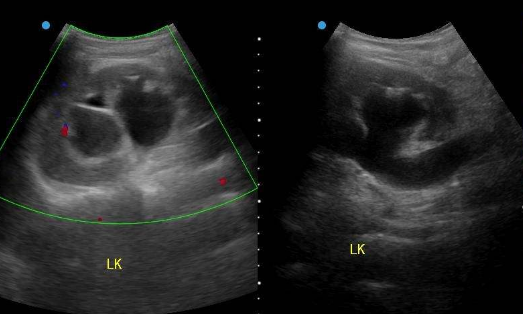

一、了解常见疾病的防范方法据我了解到的最新消息里面,输尿管结石是一种常见疾病,大部分泌尿系统结石属于这一类,绝大多数来自肾脏,包括肾结石或体外休克波后结石碎片脱落,原发性输尿管结石很少见,输尿管结石多为单发,左右两侧的发生率大致相似,双侧输尿管结石占 2% ~ 6%。临床上多见于青壮年,20 ~ 40 岁发病率最高,结石多位于输尿管下段。

常见症状为低腰痛,血尿,恶心,呕吐,还可引起上尿路梗阻,积水扩张,危及肾脏。在严重的情况下,肾功能可以逐渐丧失。常用的治疗方法是药物治疗和体外休克碎石,效果良好。形成尿结石的物质排泄增加, 长期卧床和甲状腺功能亢进患者尿中的钙增加。